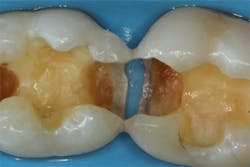

After removing the previous restorations, the distal axial wall of tooth No. 30 and the mesial axial wall of No. 31 had deep caries (figure 2). TheraCal LC (Bisco Dental)—a light-cured, resin-based liner containing calcium silicate (the active ingredient of MTA)—was placed over these areas of deep caries. A thin layer of the material was placed just at the areas of deep caries (figure 3) and light cured. Layers should be kept thin to ensure that the entire bulk of this opaque material cures, and placement should be limited to areas where needed in order to use the surrounding dentin for adhesive bonding. The dentin should be moist but not overly wet when TheraCal LC is applied to ensure that the material “sticks” to the tooth. Because this material is resin based, it is not necessary to cover this material with a separate resin-modified glass ionomer (RMGI) liner.

Figure 2: Deep caries remains on the distal axial wall of tooth No. 30 and the mesial axial wall of No. 31